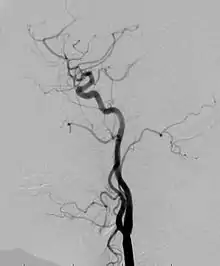

Angiogram: an angiogram can also be ordered to get a detailed look at the blood vessels in the affected or overgrown limb. In this test an interventional radiologist injects a dye into the blood vessels that will help see how the blood vessels are malformed.[23]